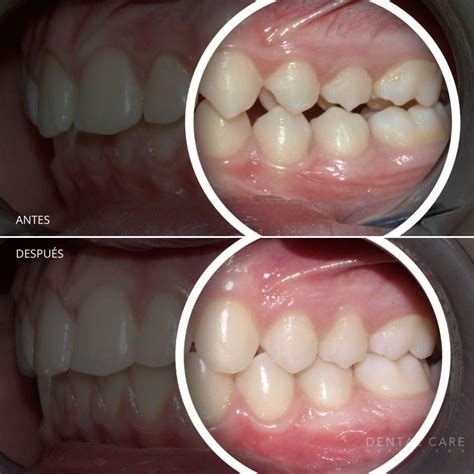

Alineadores o brackets en dientes torcidos

En jóvenes y adultos, el uso de los brackets o del aparato dental invisible es la solución definitiva para corregir los dientes torcidos. Aunque se puede iniciar un tratamiento de ortodoncia a cualquier edad, es recomendable empezar lo antes posible para evitar o arreglar los dientes torcidos. Entre los sistemas de ortodoncia más conocidos en el mercado encontramos la ortodoncia invisible, como los brackets de cerámica, de zafiro, linguales o los alineadores invisibles. También encontramos los brackets tradicionales de metal o los brackets autoligables. Todos estos aparatos dentales son útiles para el objetivo que se busca: enderezar los dientes y arreglar los problemas de maloclusión.

Tal y como mencionamos, dentro de la ortodoncia invisible encontramos los tratamientos con alineadores, como los tratamientos Impress. El uso de alineadores es un método igual de efectivo que la ortodoncia tradicional para tratar los dientes torcidos. Mediante unas fundas transparentes, los pacientes pueden alinear sus dientes de manera casi imperceptible, obteniendo resultados igual de satisfactorios que con los métodos tradicionales.